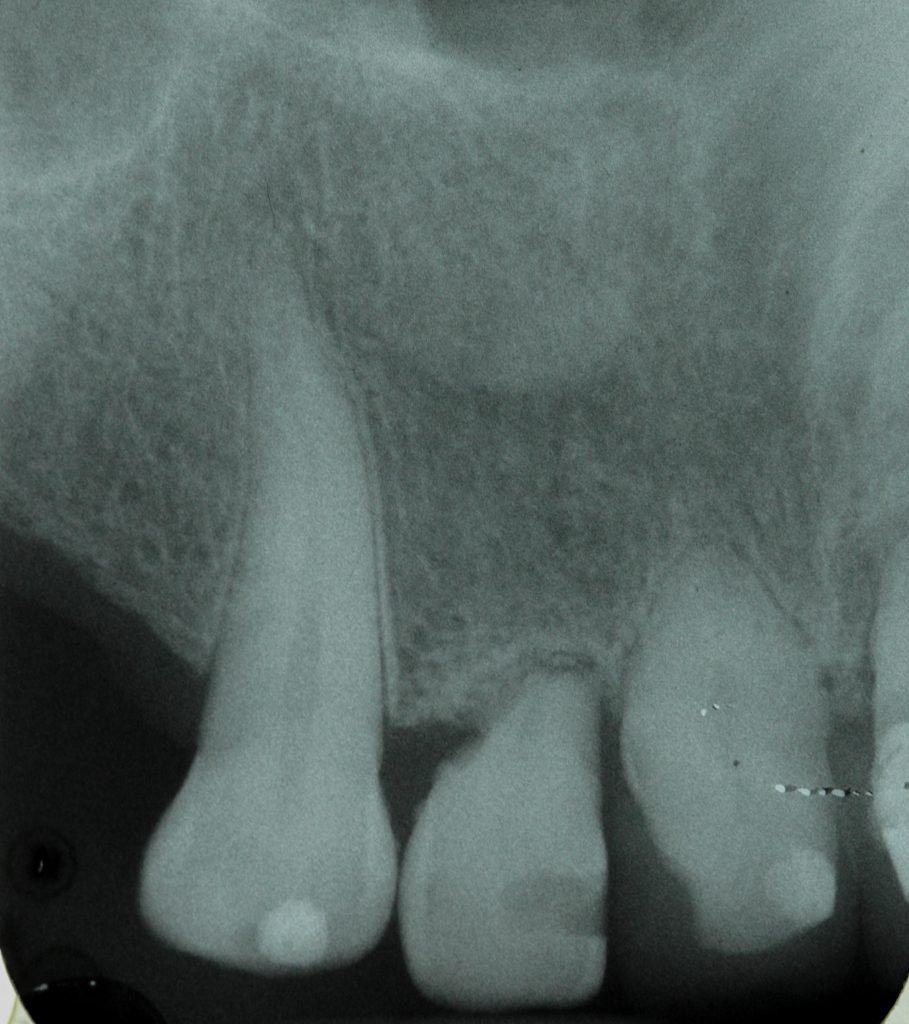

Punto Bajío Casos Clínicos Prótesis Fija sobre Implante unitario Inicio Provisional Final Prótesis Parcial Fija sobre 2 Implantes 2 Implantes Final Prótesis Bucal Removible Inicial Inicial Superior Inicial Inferior Rayos X Inicial Rayos X Inicial Frontal Final Final Superior Final Inferior Prótesis Parcial Fija/ Coronas de Circonio Sonrisa Inicial Foto Inicial Foto Inicial Inferior Foto Final Inferior Foto Final Sonrisa Final Prótesis Total Protesis Inmediatas 1 Protesis Inmediatas 2 Prótesis Removible/ Coronas Metal-Ceramica Carillas Incrustaciones Endodoncia